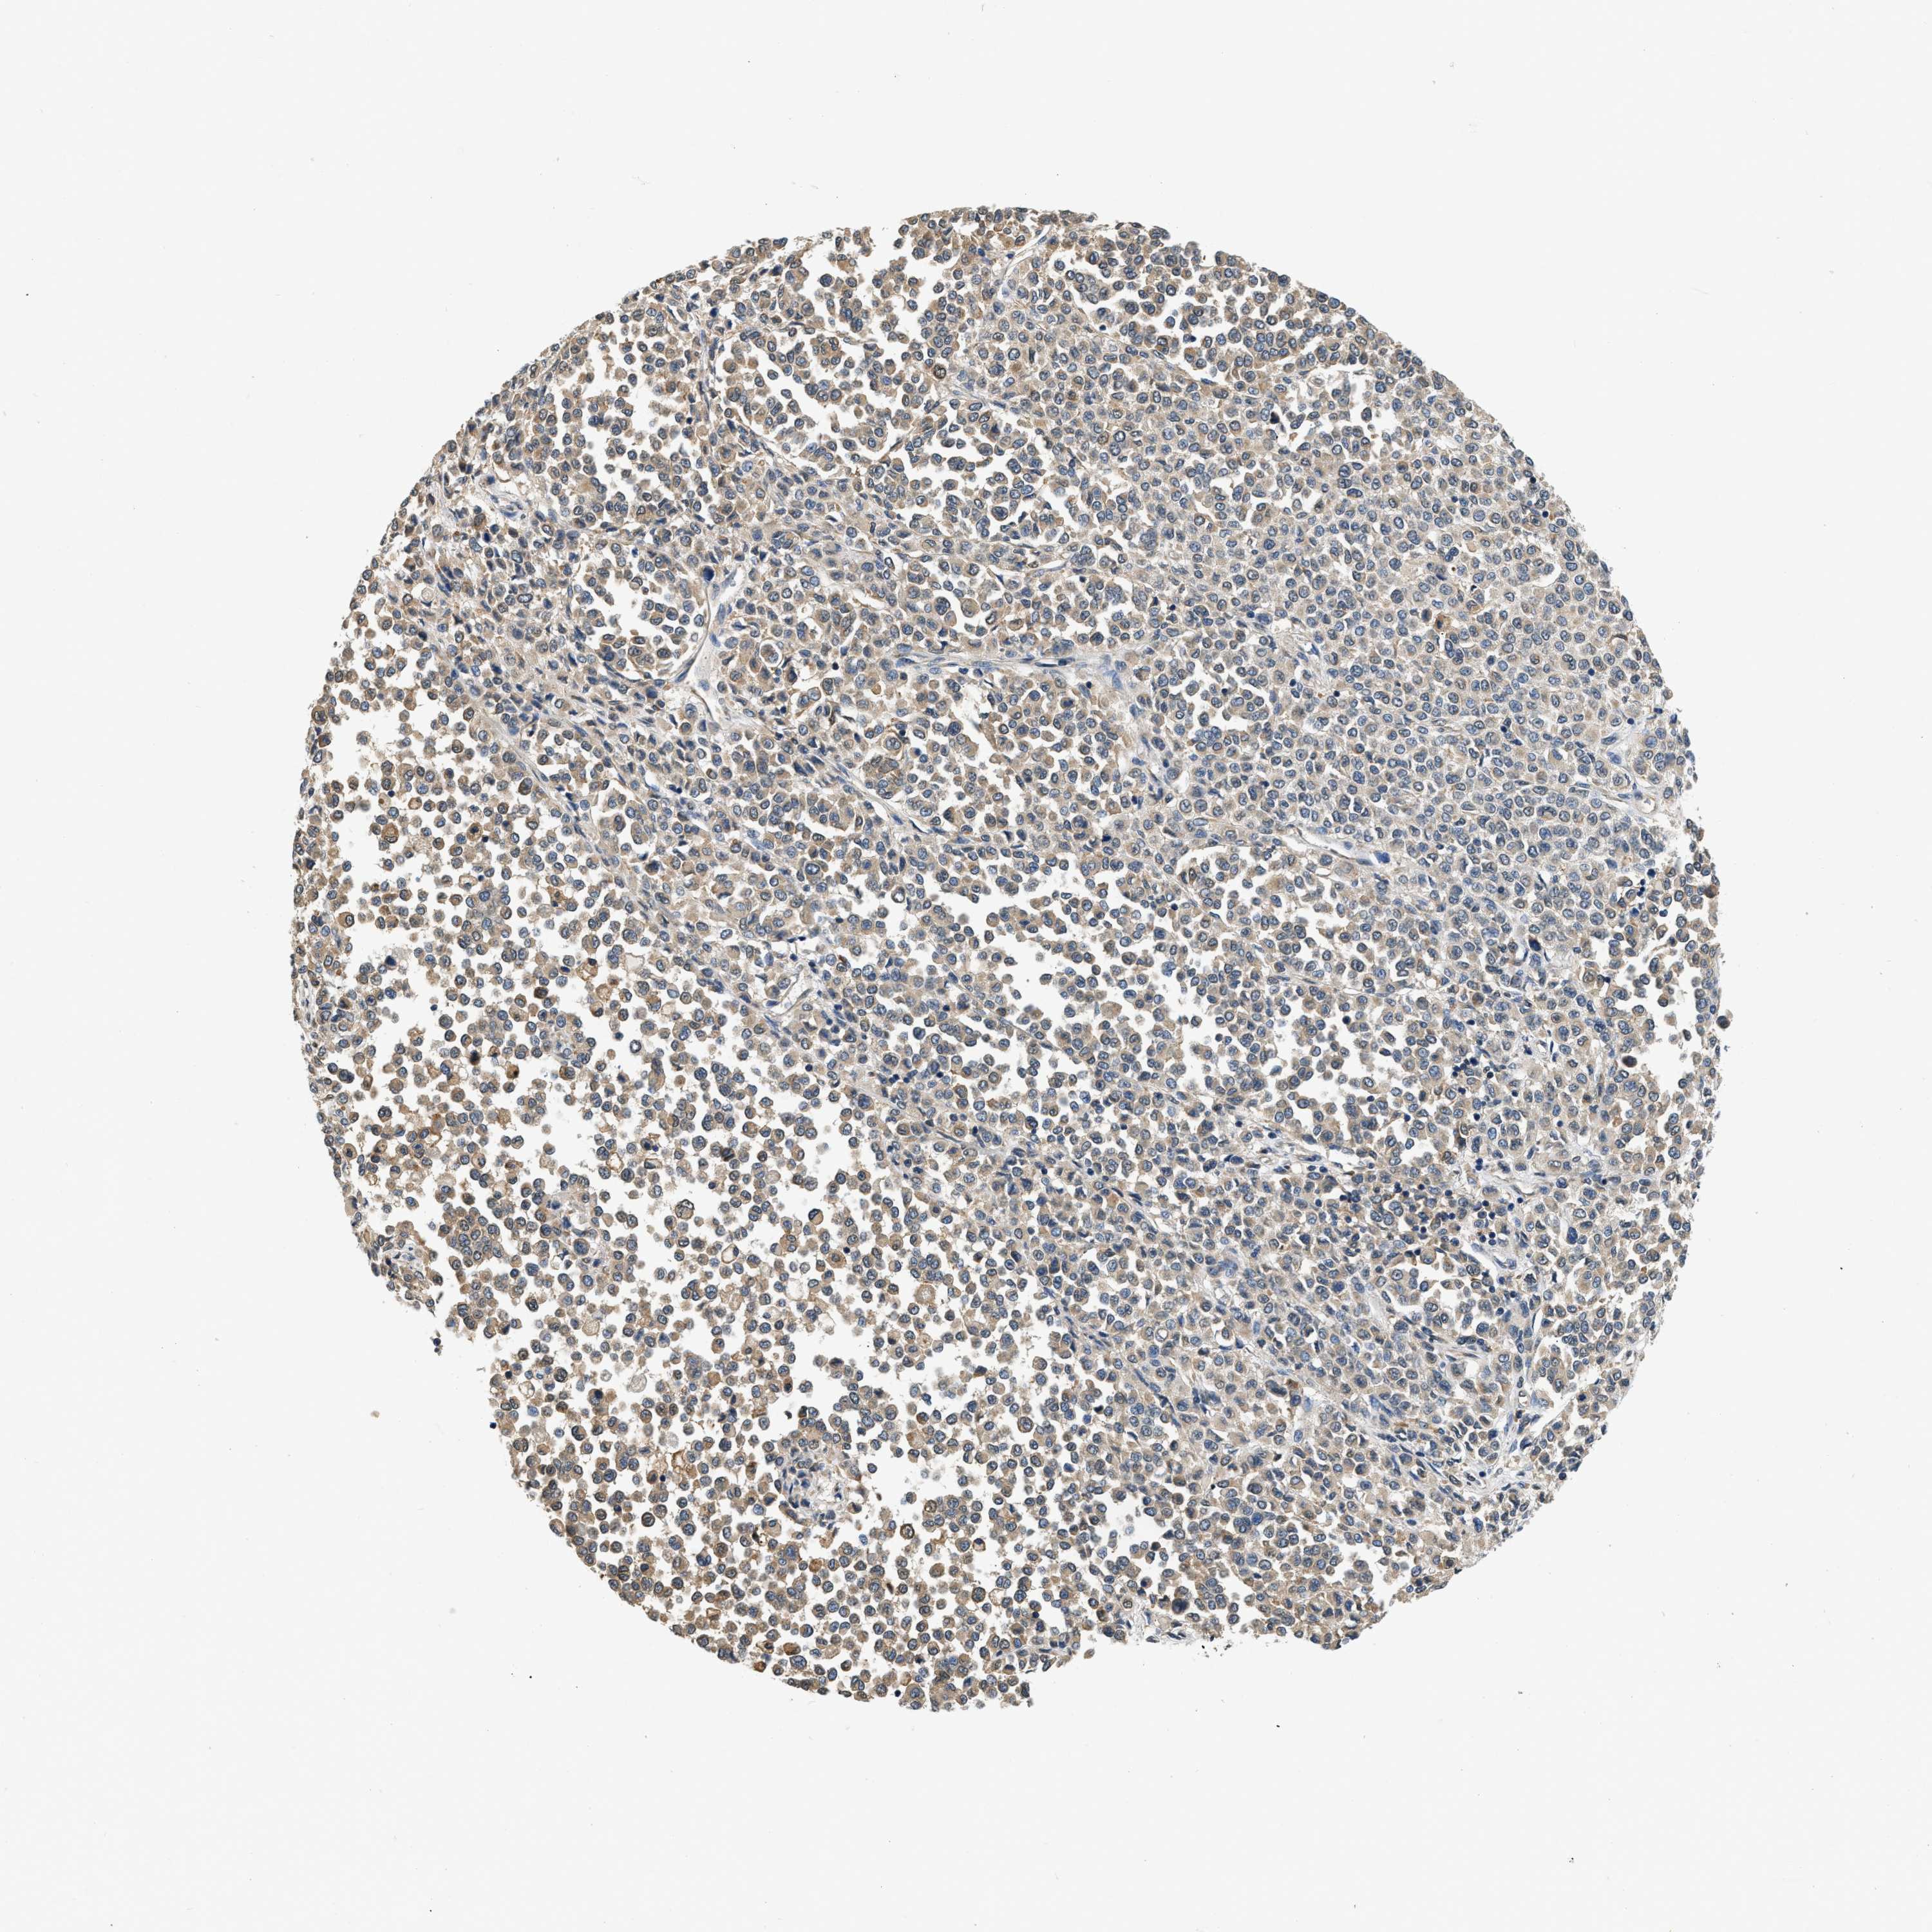

MELANOMA - Protein expressioni

A mouse-over function shows sample information and annotation data. Click on an image to view it in a full screen mode. Samples can be filtered based on level of antibody staining by selecting one or several of the following categories: high, medium, low and not detected. The assay and annotation is described here.

Note that samples used for immunohistochemistry by the Human Protein Atlas do not correspond to samples in the TCGA dataset.

Antibody stainingi

Antibody staining in the annotated cell types in the current human tissue is reported as not detected, low, medium, or high, based on conventional immunohistochemistry profiling in selected tissues. This score is based on the combination of the staining intensity and fraction of stained cells.

Each image is clickable and will lead to virtual microscopy that enables deeper exploration of all samples and also displays staining intensity scores, fraction scores and subcellular localization as well as patient and tissue information for each sample.

Antibody HPA018676

Staining

High

Medium

Low

Not detected

Intensity

Strong

Moderate

Weak

Negative

Quantity

>75%

75%-25%

<25%

None

Location

Nuclear

Cytoplasmic/membranous

Cytoplasmic/membranous,nuclear

Malignant melanoma, NOS

Malignant melanoma, Metastatic site